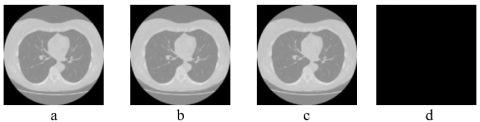

The results of the performance metrics used to evaluate the watermarked versions of the medical images are tabulated in Table 2. As seen from Table 2, it can be seen that the proposed technique has attained better imperceptibility. Figure 3 exhibits the reversibility of the content-based watermarking approach by pixel-by-pixel comparison between the cover image and the restored image, which shows no numerical difference between those images.

Figure 3. (a) Cover image, (b) Watermarked version of cover image with PSNR value 78.6 dB, (c) Restored image with PSNR value 73.84 dB, and (d) No numerical difference can be found out/identified between the host and recovered image